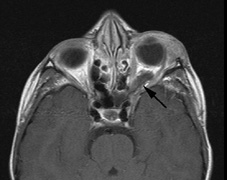

Fig. 7. Neurofibromatosis type 2: Images of a 12-year-old boy with deafness and weakness in his arms and legs, whose father has bilateral deafness. Axial T2-weighted (a) and postcontrast axial (b) T2-weighted images reveal bilateral vestibular schwannomas, which are also known as acoustic neuromas (arrows). This is the classic finding of NF2. (b, c) Bilateral schwannomas are seen in Meckel's cave (arrowheads) and a (d) lower left cranial nerve schwannoma extends into the pars nervosa of the jugular foramen (arrow). (e) A part cystic and part solid enhancing ependymoma in seen within the cervical cord and medulla and within the distal cord and conus. (e, f) Thoracic schwannomas are present at numerous levels (arrowheads). Marked enhancement and thickening of the roots within the cauda equina also represent multiple schwannomas.